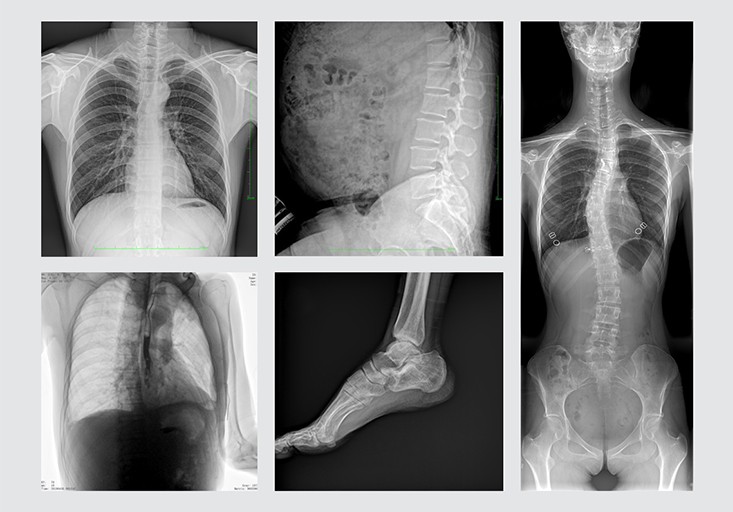

清晰的臨床圖像

多功能動(dòng)態(tài)DR展示視頻